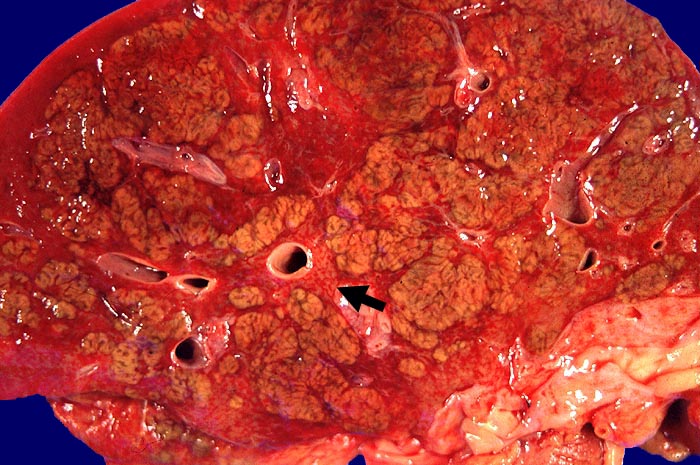

Das histologische Bild der akuten Hepatitis vom Virustyp ist gekennzeichnet durch eine lobuläre Entzündung bei fehlender portaler Fibrose und nur geringer entzündlicher Infiltration der Portalfelder. Es finden sich ballonierte Hepatozyten, Apoptosen ( 1164) und fleckige Nekrosen. Perivenuläre Nekrosen, Brückennekrosen oder konfluierende multilobuläre Nekrosen und eine läppchenzentrale Cholestase können vor allem in klinisch fulminant verlaufenden Fällen nachgewiesen werden. Zahlreiche Makrophagen, welche Diastase-PAS positives Zeroidpigment ( 4319) von phagozytierten nekrotischen Hepatozyten enthalten, zeugen im subakuten Stadium von einer abgelaufenen akuten Hepatitis mit Parenchymnekrosen. Eine Unterscheidung der verschiedenen Typen der viralen Hepatitis und einiger Formen medikamentöser Hepatitiden gelingt rein morphologisch aufgrund des unspezifischen Bildes meist nicht. Für eine ätiologische Klassifizierung sind zusätzliche klinische Angaben erforderlich (Anamnese, Medikamente, Serologie).